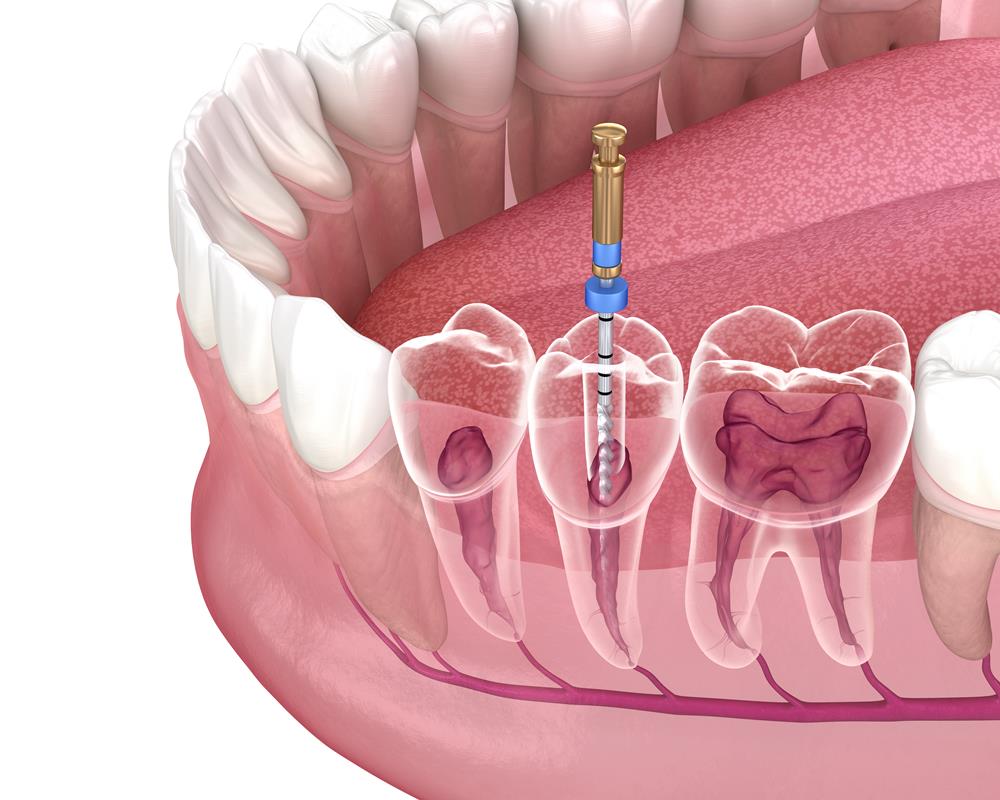

Beneath the crown of each tooth is soft tissue filled with blood vessels and nerves. This is called dental pulp. Within this inner chamber of tissue, there are also roots. These roots extend from the pulp chamber down through the gums, and they tether to the jawbone. Roots stabilize teeth, and they also deliver blood supply and nutrients to them.

Root canal therapy is a procedure that is only slightly more complex than getting a filling. The process involves:

- Numbing nerves to the treatment area with a local anesthetic.

- Removing damaged enamel and dentin using a small dental instrument.

- Accessing the root canal and using tiny dental files to remove soft tissue in canals.

- Sterilizing root canals with a liquid solution.

- Applying gutta-percha into root canals to seal them against bacterial contamination.

- Affixing a temporary crown to protect the tooth.